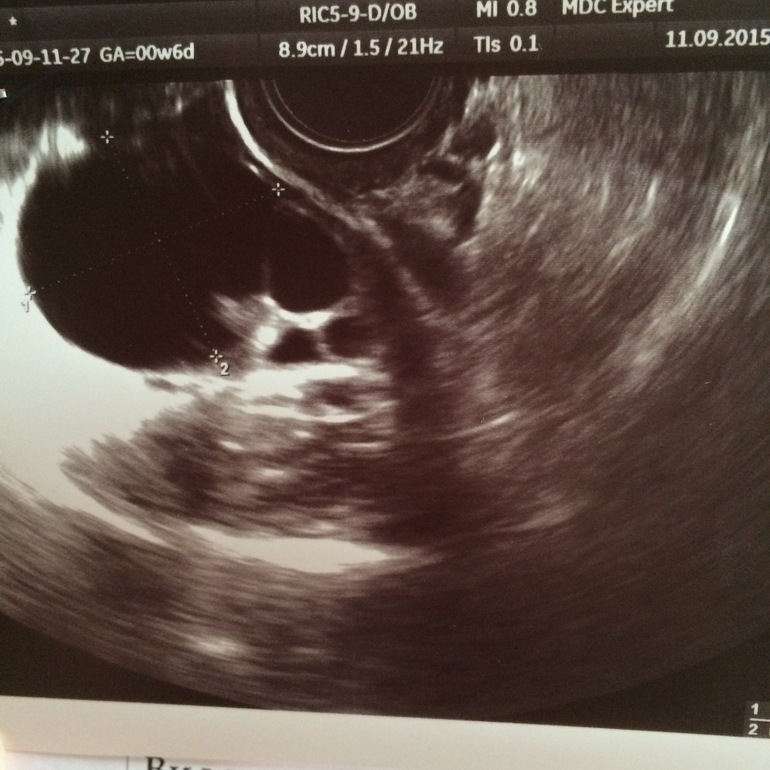

Мне помог ) вот допиваю вторую пластинку ) было 2 кисты , одной из них было вообще 2 года . Пропила пластинку , на 9 д.ц сделала узи , а там одна киста вообще рассосалась , а вторая уменьшилась на 1 см )) до этого пила Диане 35,никакого толку ...